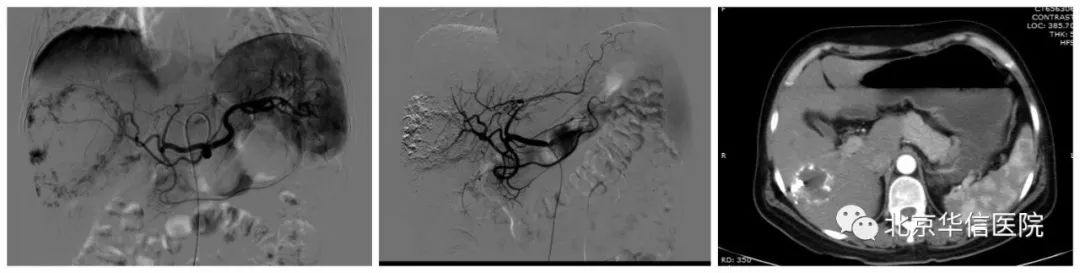

左图:栓塞前造影;中图:栓塞后造影;右图:栓塞后九个月复查CT

随后,我们采取了肝动脉造影及栓塞的方法进行治疗,经过患者右侧大腿根部不足1mm的穿刺点,将导管沿股动脉血管送入肝动脉,通过造影可见巨大的典型血管瘤染色。经微导管直接挑选肿瘤的供血血管,避开正常肝脏的供血血管,在治疗肿瘤的同时最大程度地保护正常的肝组织。栓塞完成后可见肿瘤内充满了用于治疗的碘油乳剂,而正常的肝血管、肝组织没有受到药物影响。3个月后患者通过CT复查,以前巨大的肿瘤迅速缩小到不足3cm,一切不适已完全消失。最重要的是,患者没有开刀、没有失血,仅仅通过创口还不足1mm、用时不到30分钟的微创介入手术,就达到了令患者满意的治疗效果。